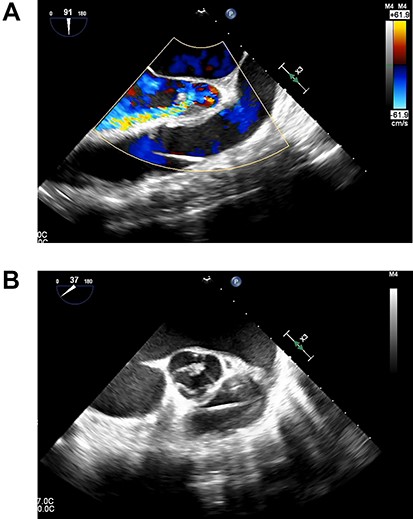

A 33-year-old man with familial dilated cardiomyopathy was urgently admitted to our hospital due to acute decompensation of heart failure with brain natriuretic peptide of 1124.5 pg/ml. Transthoracic echocardiography (TEE) showed left ventricular diastolic diameter of 75 mm, left ventricular systolic diameter of 71 mm, left ventricular ejection fraction of 20% with diffuse hypokinesis. Despite intensive medical treatment with dobutamine at 4 mcg/kg/min, his hemodynamic status did not improve: blood pressure (BP) of 91/56 (67) mm Hg, pulmonary artery pressure (PAP) of 56/18(34) mm Hg, pulmonary capillary wedge pressure of 36 mm Hg, central venous pressure (CVP) of 16 mm Hg. An Impella 5.0 catheter was emergently implanted via the right femoral artery as bridging therapy. After the initiation of Impella at the maximum flow rate, TEE showed no AI. The patient’s hemodynamic status stabilized with dopamine at 1.5 mcg/kg/min and dobutamine at 4.2 mcg/kg/min: BP of 79/66(70) mm Hg, PAP of 36/19(25) mm Hg, CVP of 9 mm Hg. Fifteen days after Impella insertion, heart transplantation was approved. HeartMate III (Abbott, Plymouth, MN, USA) implantation was performed. Intraoperative TEE detected mild AI before the Impella device was removed, which worsened to moderate AI after removal due to prolapse of noncoronary cusps (Fig. 1). At that time, BP of 107/48(67) mm Hg, PAP of 68/33(48) mm Hg and CVP of 9 mm Hg. After Park’s stitch procedure (central AV closure) was performed, diastolic arterial BP increased, with BP of 86/60(70) mm Hg, PAP of 41/25(30) mm Hg and CVP of 12 mm Hg. However, on postoperative Day 1, TEE showed the coaptation stitch on the right and noncoronary cusps had failed, causing severe AI (Fig. 2A and B). In addition, BP decreased to 84/42(49) mm Hg. Consequently, emergent AV replacement was performed. Five days after AV replacement, the patient was discharged from the intensive care unit without any complications.

(A). Transesophageal echocardiography showing severe AI at 1 day after Heart Mate III implantation. (B). Transesophageal echocardiography showing the coaptation stitch in the right and noncoronary cusps had failed at 1 day after Heart Mate III implantation.